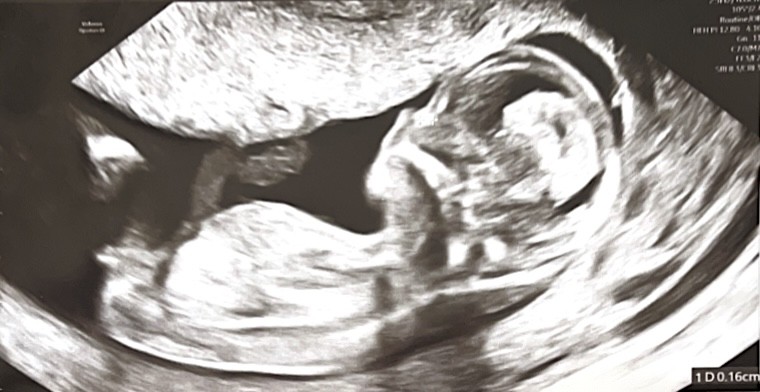

Hej listopadowe mamusie ! 🙋‍♀️ Podzielę się swoją historią. Jestem po 2 poronieniach które baaardzo źle przeszłam. Pierwsze poronienie samoistne drugie poronienie (wywoływane w szpitalu bo dzieciątko przestało się rozwijać..trauma do końca życia 🥲) Po poronieniach plik badań i kolejne miesiące starań i narastającej frustracji. Doszło do tego opóźnione owulacje w których pęcherzyki nie chciały pękać..miałam podawane zastrzyki na pęknięcie pęcherzyka(w szczęśliwym cyklu udało się z zastrzykiem). Dodatkowo okazało się, ze mam trombofilie (muszę podać zastrzyki z heparyny w brzuch żeby dzieciątko się rozwijało).

Aktualnie 13+3. Jestem taka szczęśliwa!

Jestem po pierwszych badaniach prenatalnych z wymiarów ż USG wszystko ok! Czekam na badania krwi.

Z określeniem płci dziecka ginekolog się wstrzymała 😅 Ja tu ewidentnie widzę dziewczynkę a wy co myślicie? 😀